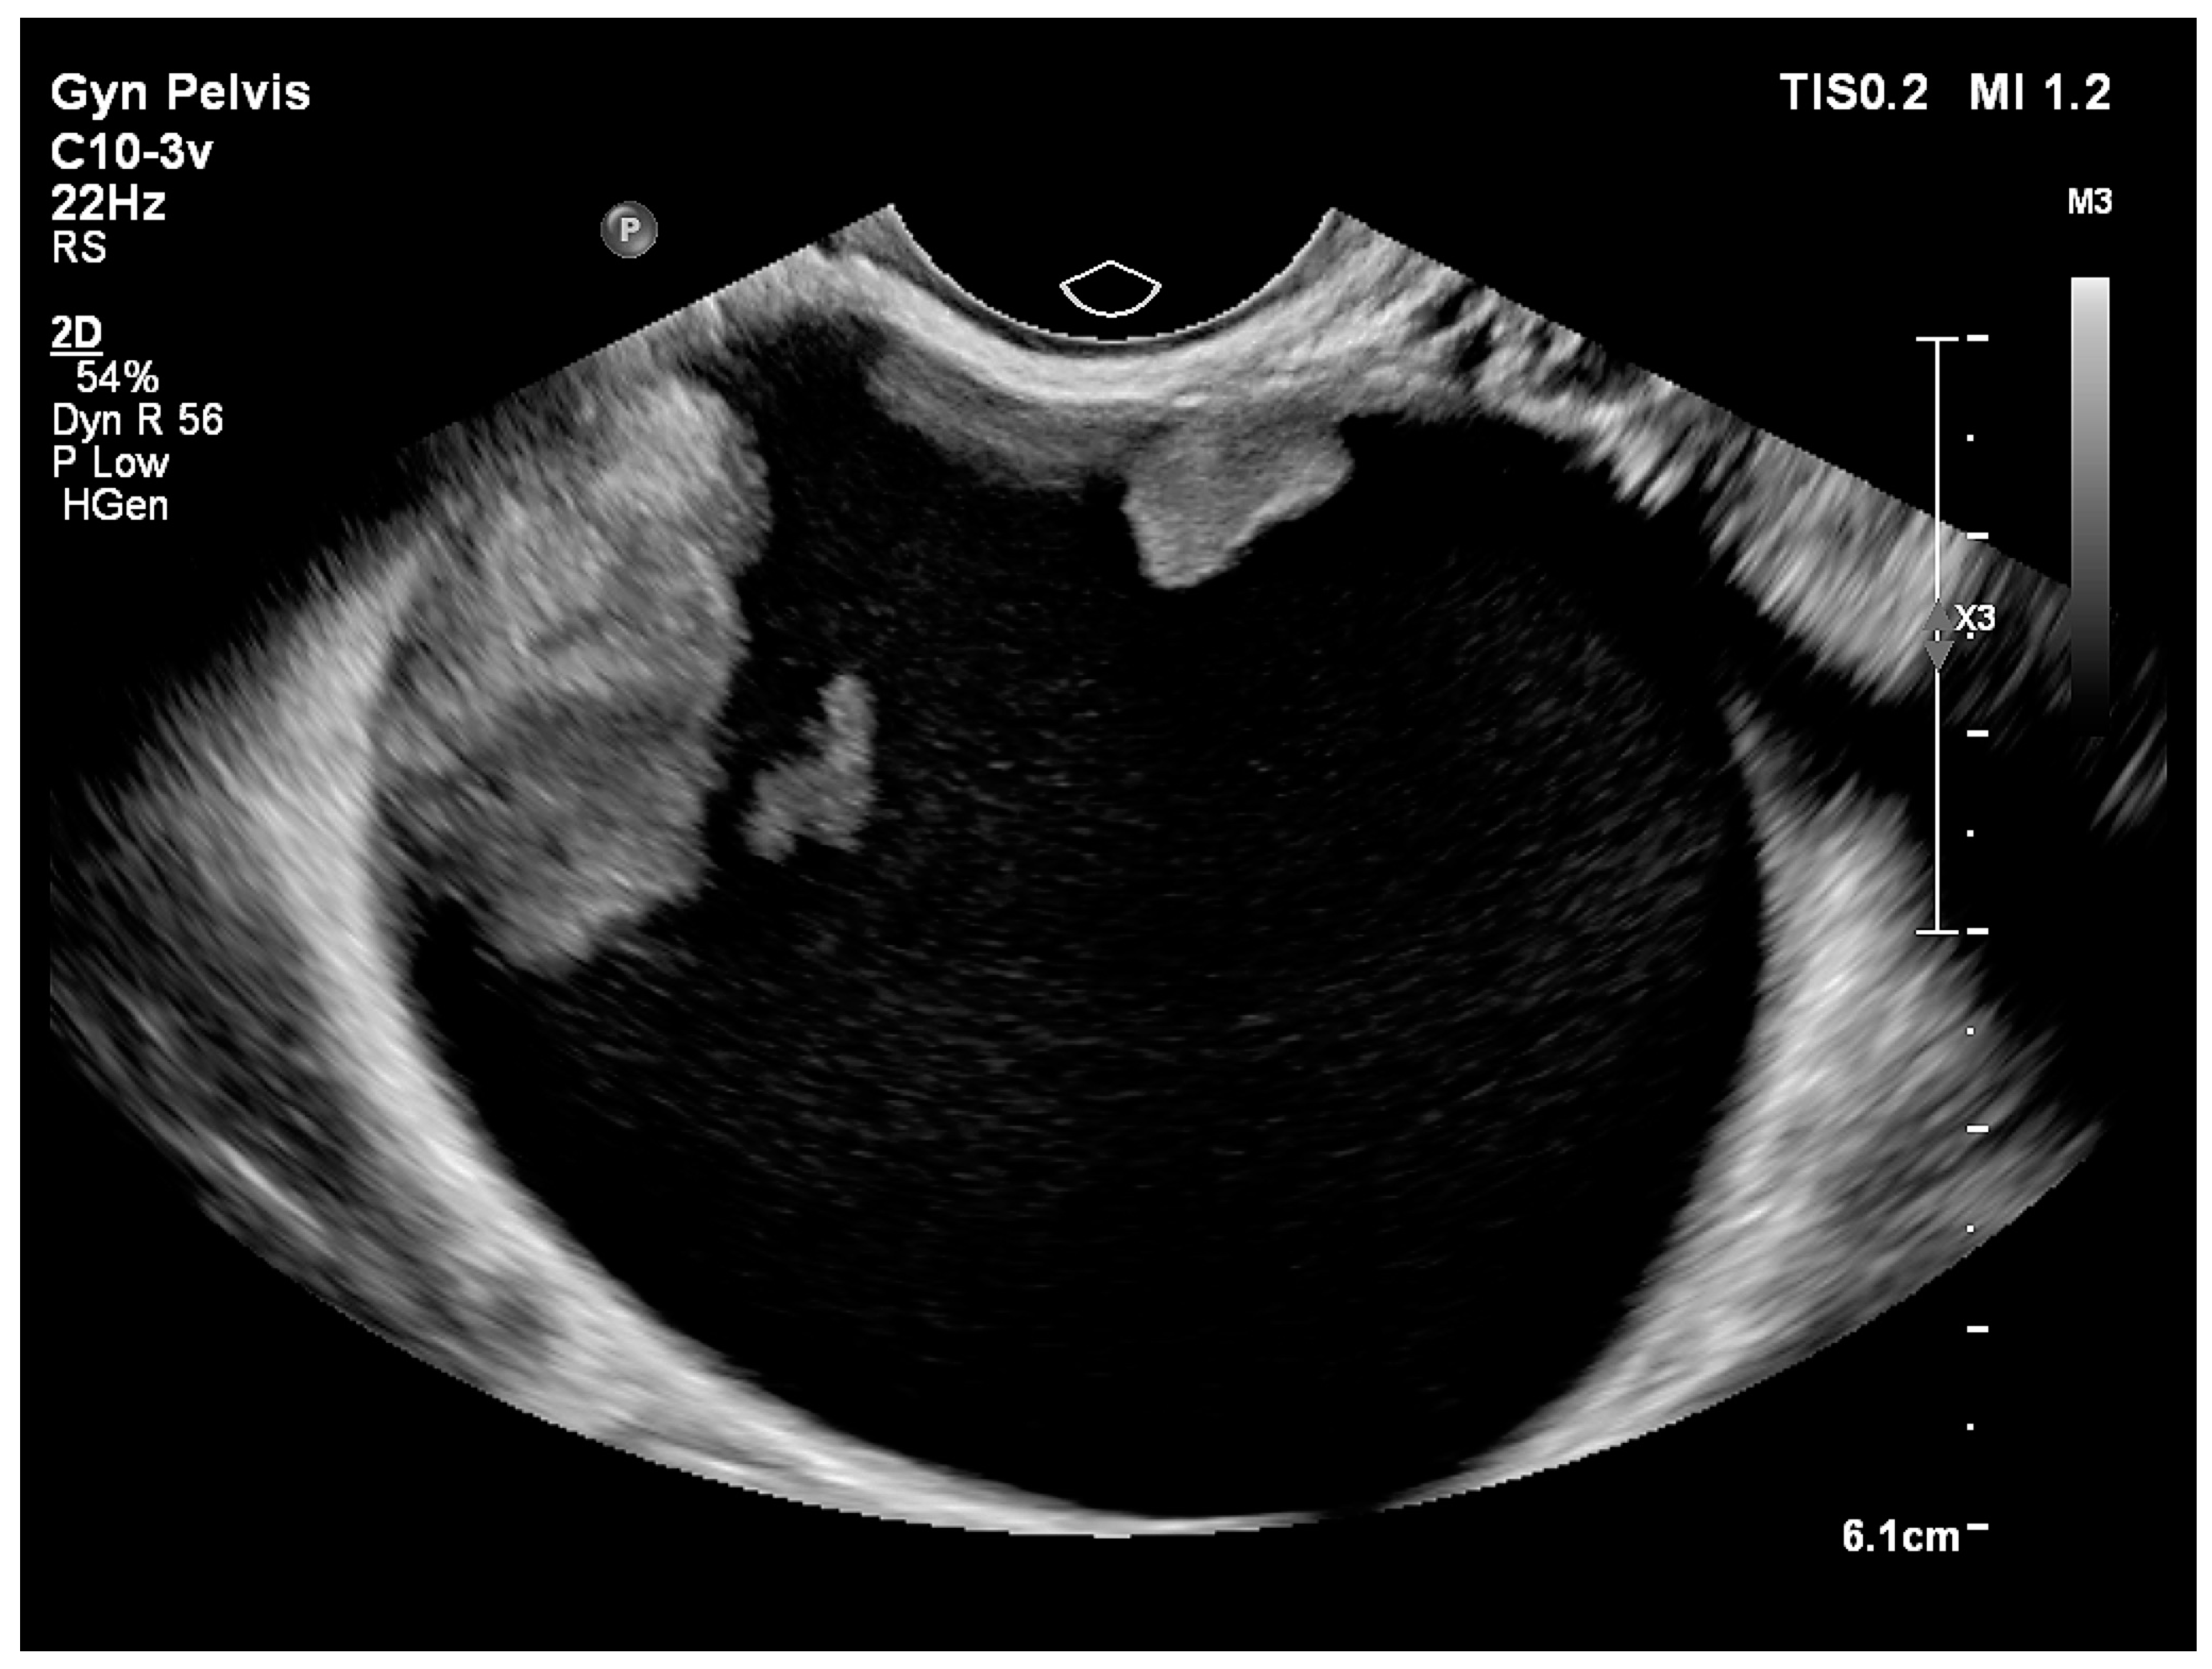

| Cystic (Figure 3) | 24 (28.2) |

| Cystic | 7 (12.3) | 12 (54.5) | |

| Cystic–solid | 50 (87.7) | 10 (45.5) | |

| Number of locules: | p = 0.008 | ||

| Uniloculcar | 32 (56.1) | 5 (22.7) | |

| Multilocular | 25 (43.9) | 17 (77.3) | |

| More than 10 locules present | 14 (24.6) | 14 (63.6) | p = 0.001 |